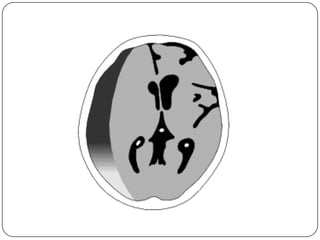

Hematoma Epidural

 Mayor incidencia en ninos que en adultos, de

origen venoso

   Forma biconvexa, lenticular

   No cruza suturas, si inserciones durales

   T.A.C. hiperdenso, heterogeneo precoz, se vuelve

homogeneo en pocas horas

   85% al 95% se asocia a fractura craneal

   Frecuentemente provoca herniaciones

Hematoma Epidural  Mayorincidencia en ninos que en adultos, de origen venoso  Forma biconvexa, lenticular  No cruza suturas, si inserciones durales  T.A.C. hiperdenso, heterogeneo precoz, se vuelve homogeneo en pocas horas  85% al 95% se asocia a fractura craneal  Frecuentemente provoca herniaciones

Hueso Dura Dura: delgada, densa, no elastica, adherida fuertemente a la tabla interna del hueso